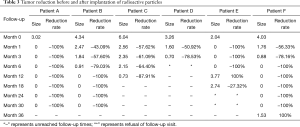

In accordance with the longest diameter of the tumors measured in radiological examination, using the longest diameter to represent tumor size (cm), reductions of tumors during follow-up are presented in Table 3.

Full table

As illustrated in Table 3, tumors were significantly reduced in all 6 patients after the implantation of radioactive particles. A typical case can be seen in Figures 4,5.

Figure 6 also shows that the tumors significantly decreased in all 6 patients after implantation of radioactive particle, which is consistent with the findings in Table 3. The most obvious decrease can be seen in the 6th month after procedure.